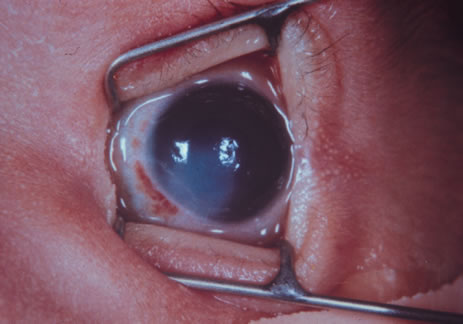

following attempted abortion. J Pediatr 46:182, 1955 58. Richardson S: The toxic effect of quinine on the eye. South Med J 29:1156, 1936 59. Slone D, Siskind V, Heinonen OP, et al: Antenatal exposure to the phenothiazines in relation to congenital malformations, prenatal

morbidity. J Pediatr Ophthalmol Strabismus 26:271, 1989 205. Alden ER, Kalina RE, Hodson WA: Transient cataracts in low birth weight infants. J Pediatr 82:314, 1973 206. Gruenwald P: Infants of low birth weight among 5,000 deliveries. Pediatrics 34:15, 1964 207. Mujsce DJ, Palmer C: Common neonatal illnesses. In HoekelmanRA, editor: Primary Pediatric Care, p. 597. Philadelphia, Mosby, 2001 208. AmericanAcademy of Pediatrics, Prevention of neonatal opthalmia. In Pickering LK (ed): 2000 Red Book: Report of the Committee on Infectious Diseases, 25th ed, p. 741. Elk Grove Village, IL, American Academy of Pediatrics, 2000 209. Crede R: Reports from the obstetrical clinic in Leipzig. Prevention of eye inflammation

in the newborn. Am J Dis Child 121:3, 1971 210. Nishida H, Risemberg HM: Silver nitrate opthalmic solution and chemical conjunctivitis. Pediatrics 56:368, 1975 211. Isenberg SJ, Apt L, Wood M: A controlled trial of povidone-iodine as prophylaxis against opthalmia

neonatorum. N Engl J Med 332:562, 1995 212. Alexander ER, Harrison HR: Role of Chlamydia trachomatis in perinatal infection. Rev Infect Dis 5:713, 1983 213. Weiss SG, Newcomb RW, Beem MO: Pulmonary assessment of children after chlamydial pneumonia of infancy. J Pediatr 108:659, 1986 214. Hammerschlag MR: Chlamydial infections. J Pediatr 114:727, 1989 215. Rosales T, Leake R, Isenberg S, et al: Systematic effects of mydriatics in lower-weight infants. J Pediatr Opthalmol Strabismus 18:42, 1981 216. Isenberg S, Everett S: Cardiovascular effects of myodriatics in low-birth-weight